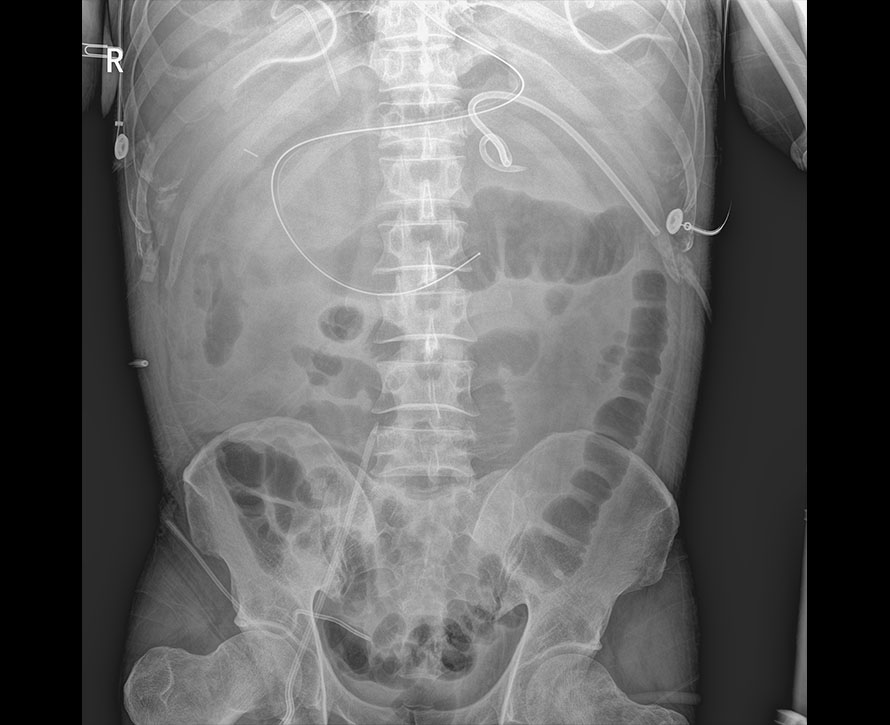

临床图像